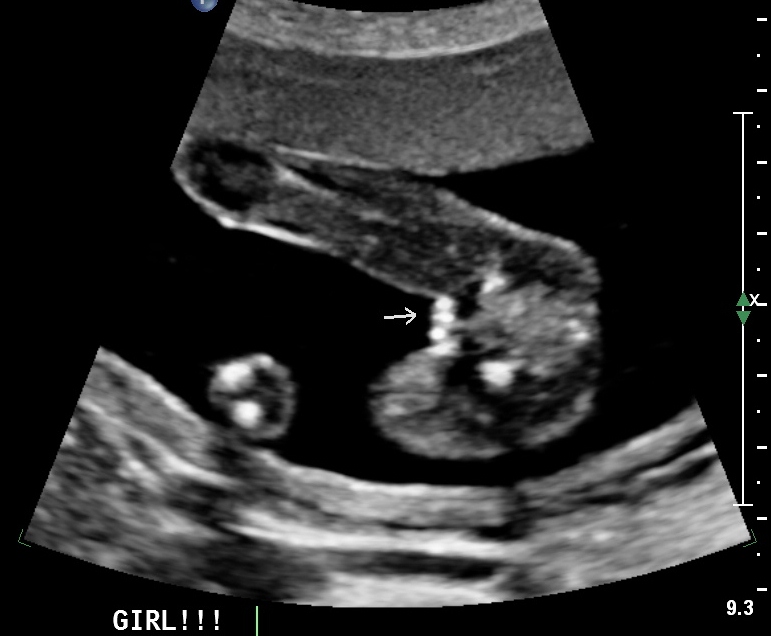

I had 100% Girl guesses on my NT nub shot. Good job girls, you were all right! The first photo is from my anatomy scan at 18wks 6days. The second photo is from my 12wks 0days NT scan. I found it really helpful to see updates/confirmed shots so here goes. Thanks everyone!!

Attachment 7281

Attachment 7282